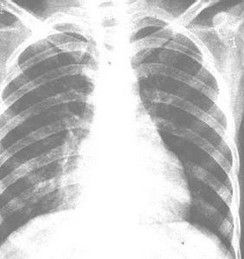

肺炎克雷伯菌單菌落為革蘭陰性桿菌,病變中滲出液粘稠而重,致使葉間隙下墜。細菌具有莢膜,在肺泡內生長繁殖時,引起組織壞死、液化、形成單個或多發性膿腫。病變累及胸膜、心包時,可引起滲出性或膿性積液。病灶纖維組織增生活躍,易於機化;纖維素性胸腔積液可早期出現粘連。在院內感染的敗血症中,克雷伯桿菌以及綠膿桿菌和沙雷氏菌等均為重要病原菌,病死率較高。